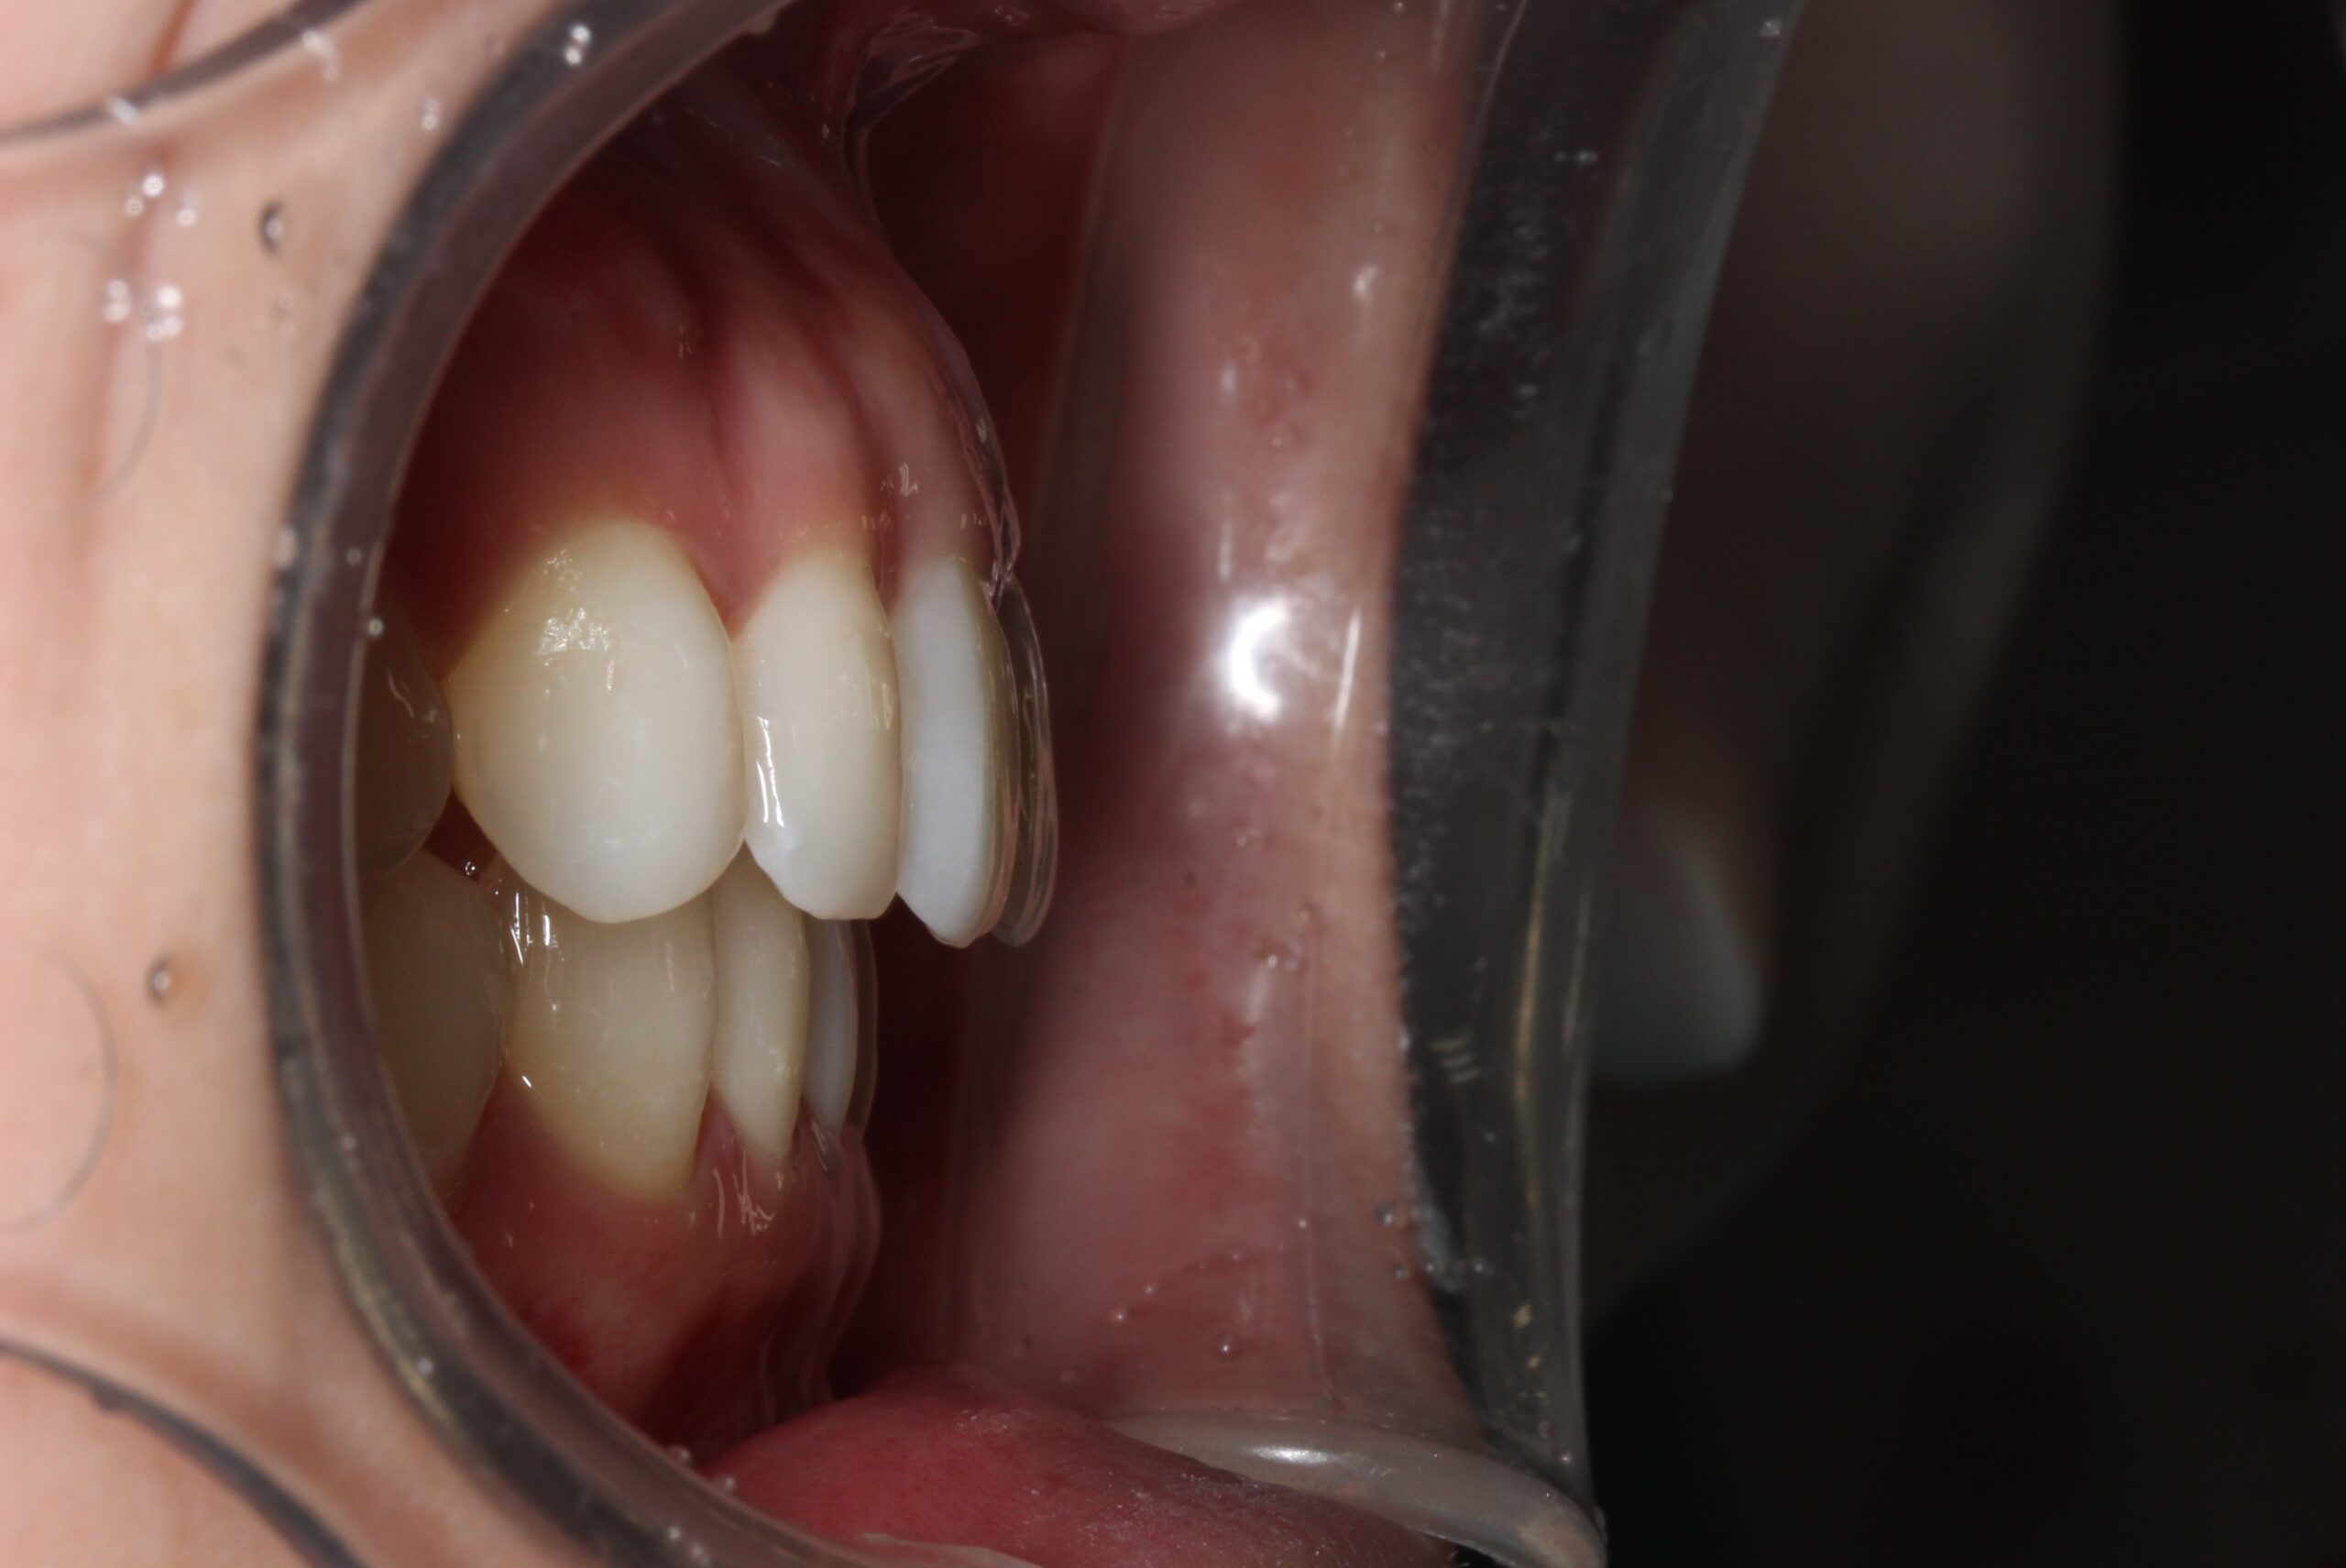

矯正術前:右側

矯正術後:右側